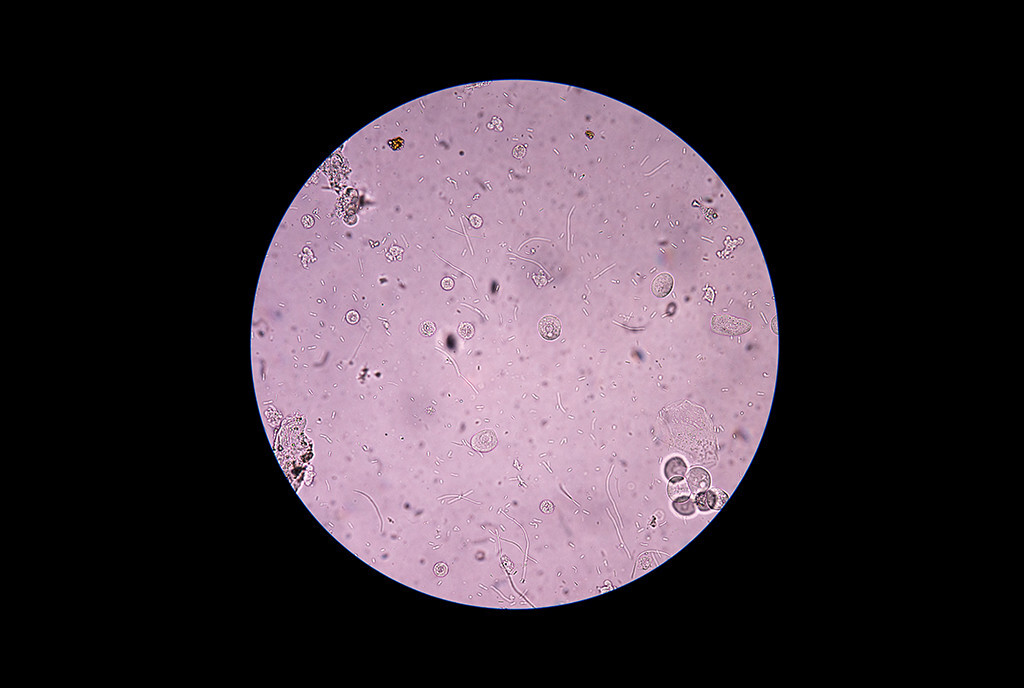

Escherichia Coli Stockfotos und bilder Kaufen Alamy

E Coli Stockfotos und bilder Kaufen Alamy

E Coli Bakterien Stockfotos und bilder Kaufen Alamy